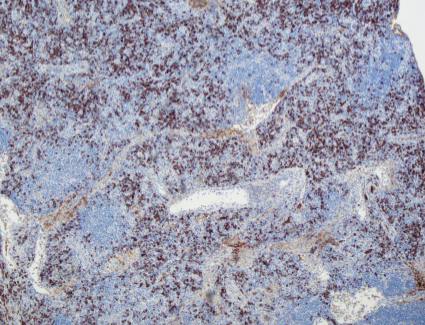

Kappa

Lambda

IgG4

HHV8

The low power view shows lymph node tissue with abnormal follicles, including partial hyalinization, regression of germinal centers, and concentric mantle zone lymphocytes showing "onion skinning" appearance. Several follicles show prominent penetrating venules. No Hodgkin-Reed-Sternberg cells or LP cells were identified.

Immunohistochemical staining shows a polytypic plasmacytosis with no increase in IgG4+ plasma cells. HHV8 staining is negative.